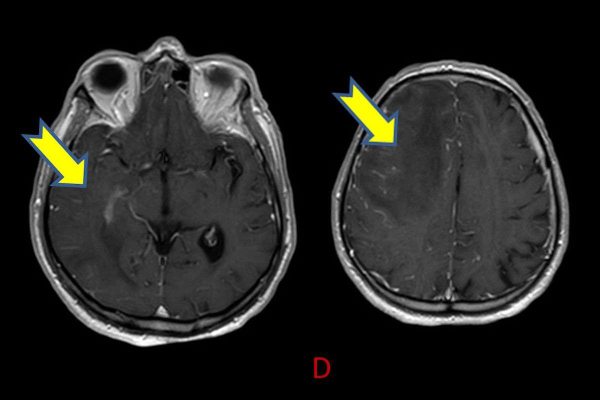

- A) Aksiyel planda FLAIR sekansta asimetrik kortiko-subkortikal vazojenik ödemi düşündüren yüksek sinyalli hafif ekspansil lezyonlar (turuncu ok).

- B) ADC haritasında kolaylaşmış difüzyon (mavi ok).

- C) Gradient seride milimetrik hemosiderin kalıntıları ve süperfisyal siderozis (kırmızı ok)

- D) Kontrastlı T1A sekansta hafif leptomeningeal boyanma (sarı ok).